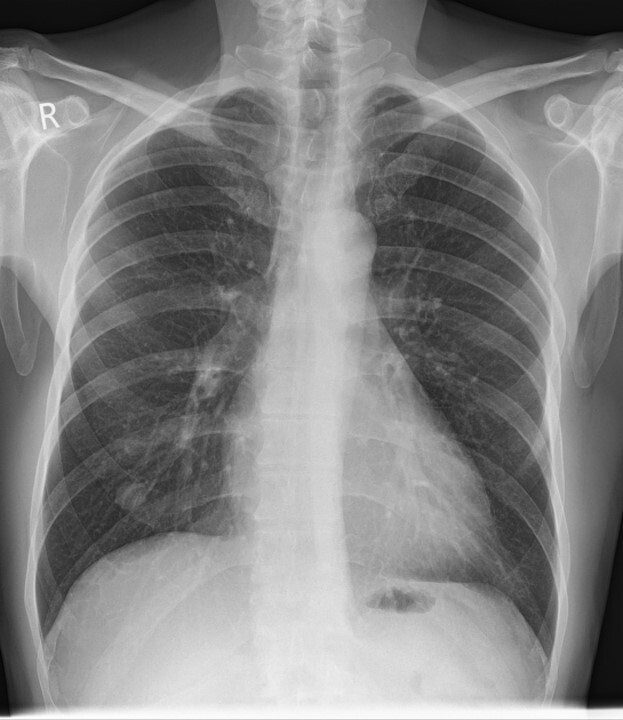

Q

x ray

A

-is this a nodule or a nipple shadow

-right lower

-squamous cell carcinoma -> strip blood supply -> necrosis

-cyst or abscess

-air fluid level

10

-nipples